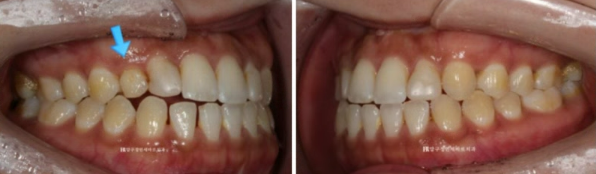

23.02

오른쪽 송곳니 파란 화살표 부분에 유치가 남아있는 환자분입니다.

영구치 송곳니가 없어서 그렇습니다.

반대쪽 같은 부위 정상 송곳니에 비하여 사이즈가 많이 작습니다.

유치라 어쩔 수 없지만 앞니 부분교정으로 적절하게 공간을 벌어주면 무삭제 라미네이트 젤라미로 송곳니만큼 사이즈를 회복할 수 있습니다.

가운데 말고 옆 앞니에 얼룩덜룩한 부분은 레진으로 왜소치를 치료한 흔적입니다.

레진은 시간이 지나면 변색이 되는 단점이 있습니다.

그래서 이번 기회에 오래된 레진을 제거하고 무삭제 라미네이트 젤라미를 하셨습니다.